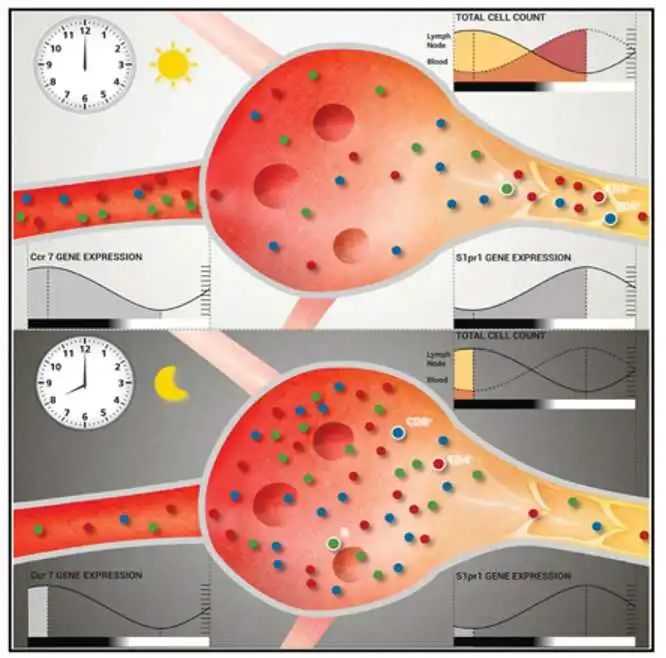

最新的研究也证实了,这三种细胞的也是日出而作日落而息,两点一线穿梭在血管和淋巴结之间。

图片摘要:The Sleep-Immune Crosstalk in Health and Disease。免疫细胞白天在血管里工作,晚上回到淋巴结里休息

如果熬夜工作熬夜运动,血液里的免疫细胞数量和活性不足,就会有更高的生病风险,同时也会影响淋巴结里免疫细胞适应性免疫反应的效率。